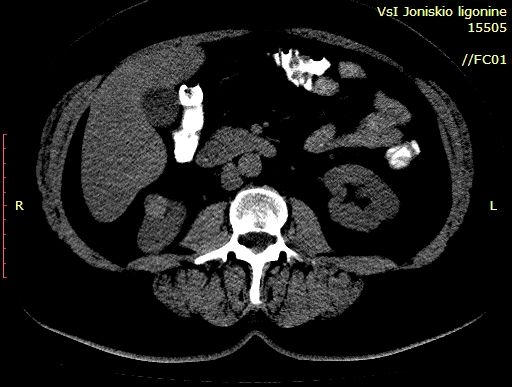

Выполнена КТ с контрастированием.

Гистология - ангиомиолипома (выполнена резекция опухоли).